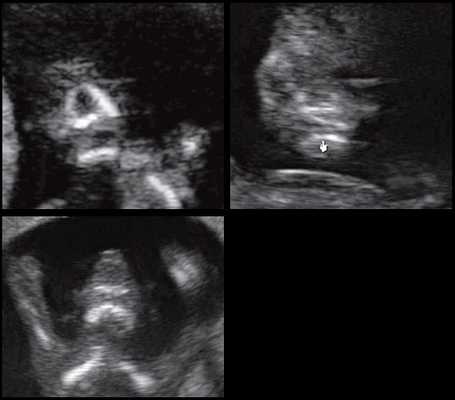

(Слева) УЗИ плода в III триместре, поперечная плоскость, косой срез. Околоплодные воды отсутствуют, определяются увеличенные гиперэхогенные почки.

(Справа) Тот же плод. УЗИ головного мозга. Определяются признаки мальформации Денди-Уокера: расхождение полушарий мозжечка, отсутствие червя, наличие крупной кисты в ЗЧЯ и вентрикуломегалия. Несмотря на то что характерной находкой для синдрома Меккеля-Грубера является затылочное энцефалоцеле, возможны и другие аномалии ЦНС.